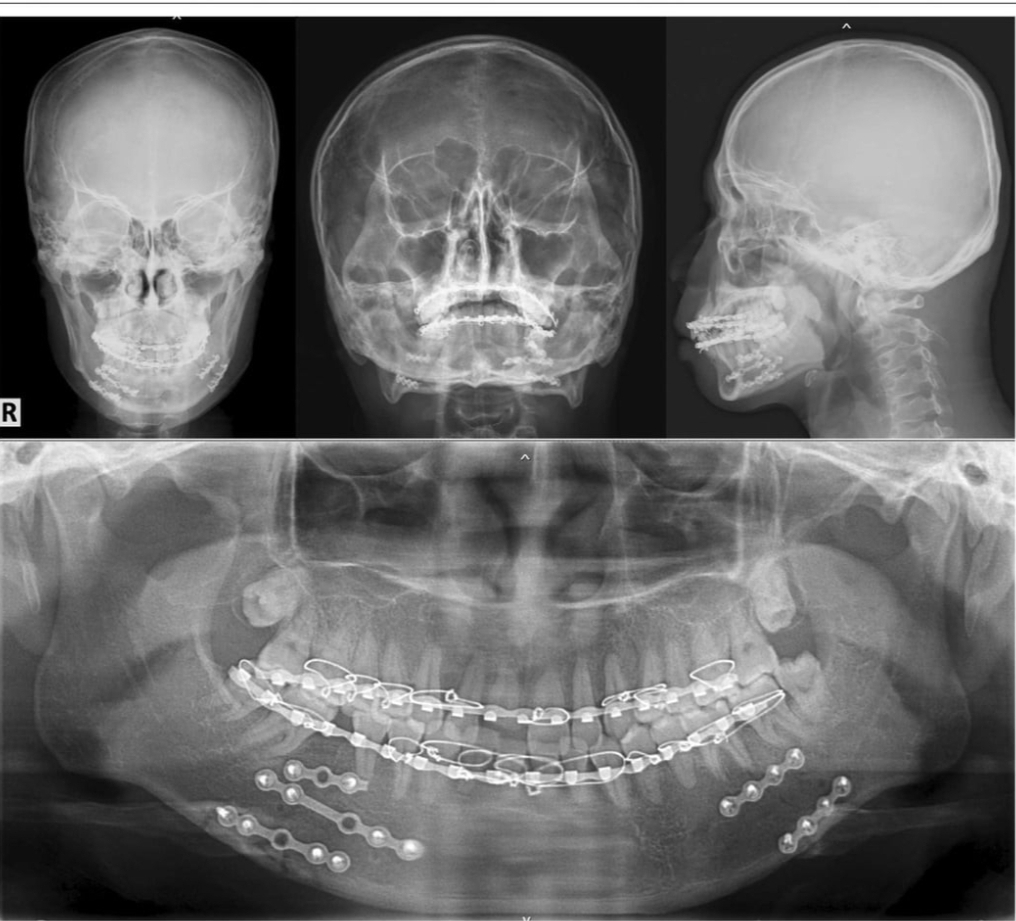

Alcohol and Firecrackers! Drunk man almost loses his jaw for putting firecrackers in his mouth.

This new year is going to be crazy.

Pretty good job the doctors did.

Mental problems lead to dental problems...

They did a damn good job